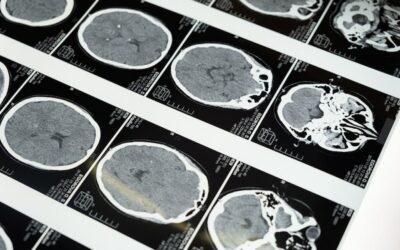

La medicina può prevedere l’ansia con l’analisi della materia grigia

Secondo lo studio condotto dai ricercatori dell’università di Trento e pubblicato sulla rivista...